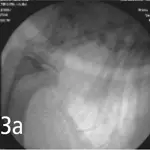

Fluoroscopic examination demonstrates thickening of the soft palate, without evidence of elongation, and thickening of the retropharyngeal tissues with near-total obliteration of the naso- and oropharyngeal air passages during inspiration. The patient's cervical trachea shows moderate variation in diameter during respiration. A cough could not be induced during this procedure.

Figure 3. Spot films from fluoroscopic study demonstrating maximal change in tracheal diameter that occurred in this dog. A cough could not be induced during this procedure.